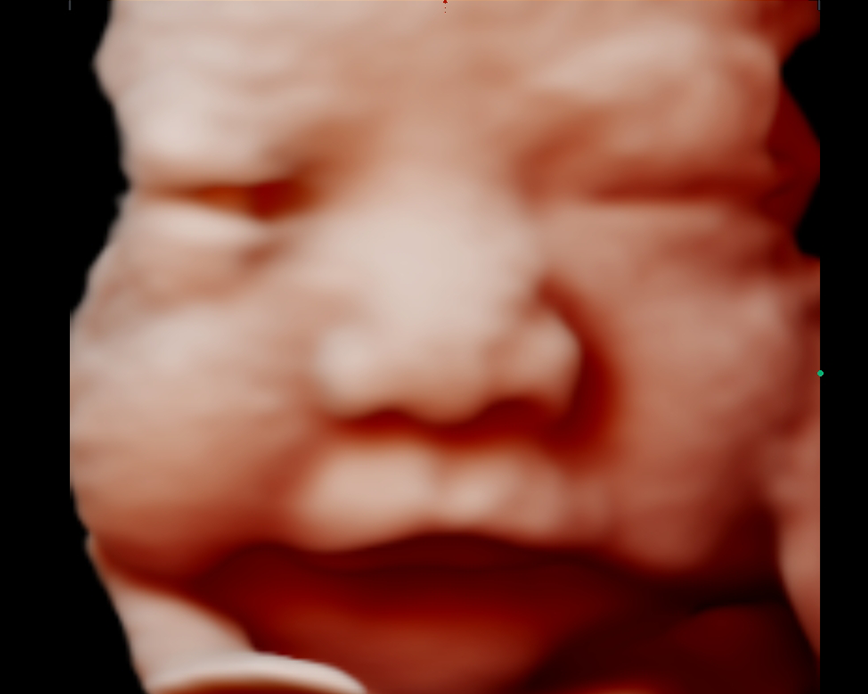

Con nuestra tecnología 5D y 6D de alta resolución, podrás ver la carita, las manos, los pies, la columna y el sexo de tu bebé con imágenes de alta calidad. Además, podrás apreciar los gestos de tu bebé en tiempo real. Esta ecografía también nos ayuda a detectar las malformaciones congénitas que pudiera tener el feto.